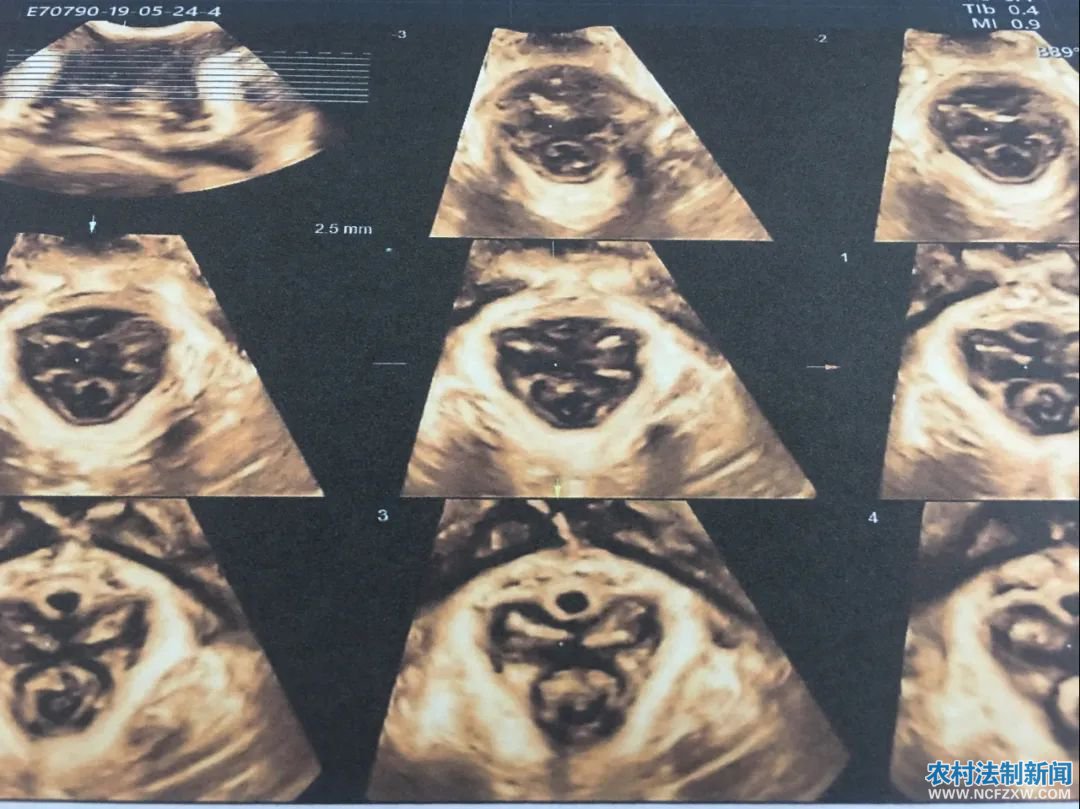

对于盆底肌撕裂等功能异常出现的压力性尿失禁、膀胱膨出、子宫脱垂等疾病,实时三维盆底超声检查能够做出准确诊断,并且具有安全无辐射、无痛苦等优点,是目前国内外了解盆底状态的重要检查方法。

盆底实时三维超声检查优势

通过盆底超声检查我们能早期发现、早期诊断盆底功能障碍性疾病,在临床症状出现前或症状较轻时通过物理治疗(盆底肌锻炼、生物反馈治疗)来恢复盆底支持结构的功能,避免或延缓手术治疗,提高患者生活质量,同时减轻家庭和社会的医疗经济负担。让“小毛病”不再“大痛苦”。